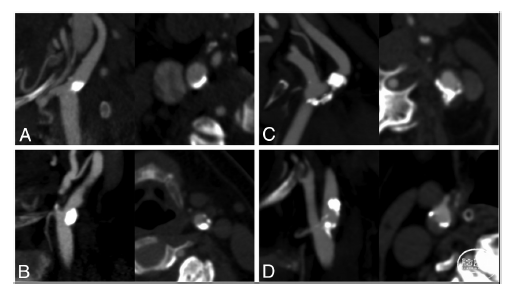

作者通过急性缺血性脑卒中患者行血栓切除术治疗的系统评价(systematic evaluation of patients treated with neurothrombectomy devices for acute ischemic stroke,STRATIS)研究数据,这是一项前瞻性、非随机性研究,研究对象为采用机械性血栓切除术的患者。比较了心源性栓塞性卒中和不明来源栓塞性卒中(ESUS)患者中同侧和对侧nsCP的患病率,并且在有同侧卒中组和无同侧卒中组2个亚组中进一步进行了其斑块特征对比。使用单因素和多因素logistic回归分析2个亚组nsCP、斑块特征(图 1)及同侧卒中之间的相互关系。

图1. nsCP患者颈内动脉斑块特征评估